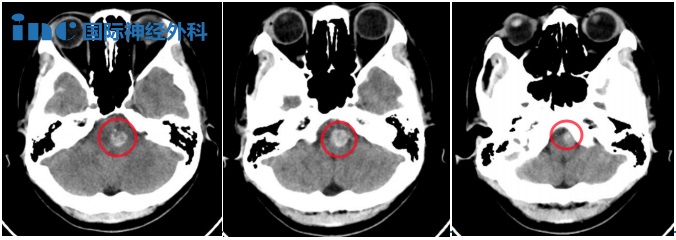

▼2023年11月头颅CT